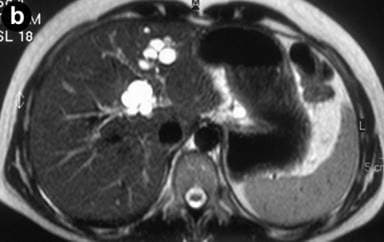

Caroli’s disease is a rare, inherited liver disorder. It causes cystic widening of the large bile ducts within the liver. How it affects the body The bile ducts become enlarged, which can impair bile flow and liver function. It may lead to bile stasis, infection, or formation of stones. Causes It is inherited and linked to abnormal embryonic development. Caroli’s disease is part of a group of fibrocystic liver disorders.